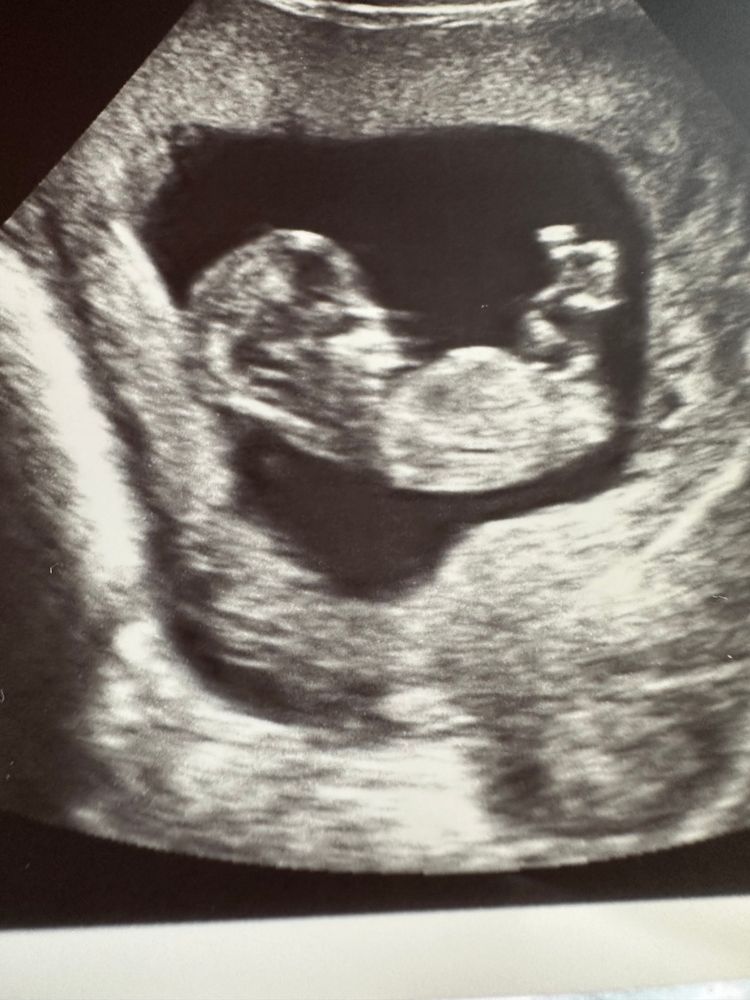

Мальчик или девочка в 12 недель?

Полового бугорка не видно, везде ножки наверх подняты. Но по форме головки, мне кажется, девочка

Похоже на девочку